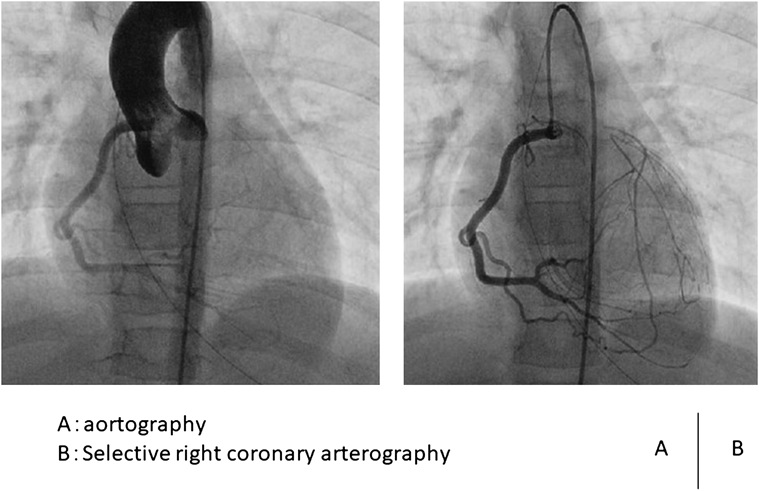

Based on the above findings, we strongly suspected myocardial ischemia. We therefore performed cardiac catheterization and cardiovascular angiography. On left ventricular imaging, the left ventricular end-diastolic volume was 44.4 mL (86% of our normal value), and the ejection fraction was 68.3%. The degree of MR was Sellers II. There was no abnormality in the wall movement. On aortography, the left coronary origin was not detected. On selective right coronary angiography, the left main coronary artery was retrogradely contrasted via collateral circulation (Fig. 4). We diagnosed her with atresia of the left coronary artery ostium based on the results of cardiovascular angiography. Two months later, she underwent bypass surgery with the left internal thoracic artery anastomosed to the left anterior descending coronary artery and mitral valvuloplasty.

Journal of Pediatric Cardiology and Cardiac Surgery 5(1): 7-11 (2021)

Fig. 4 Cardiac catheterization and cardiovascular angiography

(A) Aortography. The left coronary artery origin was not imaged. Collateral circulation from the right coronary artery to the left coronary artery was imaged. (B) Selective right coronary angiography. The left main coronary artery was imaged via the collateral circulation.